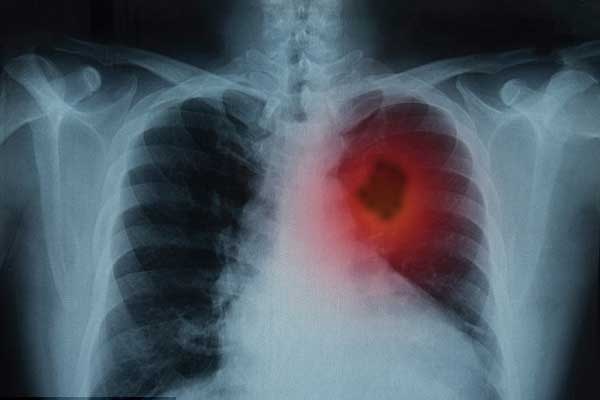

إيلاف: أظهرت الدراسة الرائدة التي أجراها الباحثون أن العلاج أدى إلى انكماش الأورام في أكثر من نصف المصابات بسرطان المبيض المتقدم، كما كان فعالًا ضد سرطان الرئة أيضًا، كما أفادت صحيفة "دايلي مايل".

وأعلن علماء في معهد أبحاث السرطان في لندن ومؤسسة رويال مارسدن للخدمات الصحية أن نتائج العلاج المركب من دوائين يُستخدمان في العلاج الكيميائي للسرطان كانت "واعدة"، مشيرين إلى أنه أوقف نمو سرطان المبيض لمدة ستة أشهر، وأدى إلى انكماش بعض الأورام.

أكد العلماء أن العلاج المركب أدى إلى انكماش ما لا يقل عن 30 في المئة من حجم أورام أكثر من نصف المصابات بسرطان المبيض (52 في المئة)، وأكثر من ثلث المصابين بسرطان الرئة (35 في المئة). وأوقف العلاج نمو هذين النوعين من السرطان لمدة متوسطها 5.8 شهر.

نقلت صحيفة "دايلي مايل" عن البروفيسور أوداي بانيرجي من وحدة تطوير الأدوية في معهد أبحاث السرطان قوله: "إننا جمعنا بين العلاج الكيميائي ودواء موجَّه يمنع الخلايا السرطانية من الرد على العلاج للبقاء. وما رأيناه كان مثيرًا للغاية. إذ انكمشت أورام أكثر من نصف المصابات بسرطان المبيض، وأكثر من ثلث المصابين بسرطان الرئة، وهؤلاء هم مرضى استنفدوا كل الخيارات الأخرى".